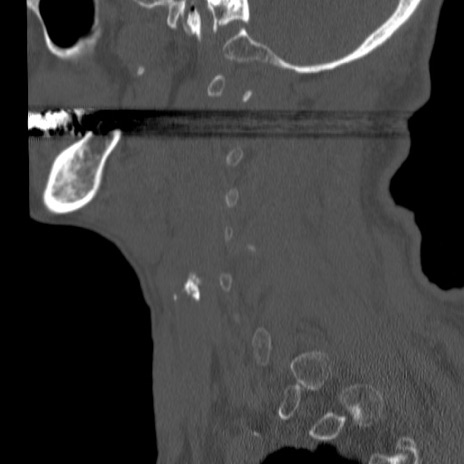

症例46 頚椎CT(矢状断像)

【症例】80歳代男性

【主訴】両側頚部〜上肢のしびれ

【現病歴】昨日、自宅内で転倒、その後より上記症状あり。意識障害なし。

【身体所見】両側上肢のallodynia(熱痛覚過敏)あり。MMTおよびDTRは正確な所見取れず。両上肢の挙上はなんとか可能。

異常所見と診断は?